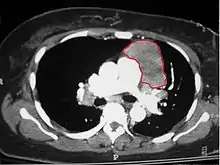

В группу опухолей средостения входят новообразования различной структуры и злокачественности, находящиеся в анатомических пределах средостения и имеющих внеорганное происхождение. К новообразованиям заднего средостения относятся лимфомы, тимомы и метастатические карциномы.

В число объёмных образований переднего средостения входят тимома, лимфома, феохромоцитома и дизэмбриогенетические опухоли (тератома и др.). Объёмные образования переднего средостения имеют более высокий риск злокачественности, чем объёмные образования других локализаций.[1][2]

Среди опухолей среднего средостения выделяют лимфому, метастатическую карциному, тератодермоидную кисту, бронхогенную кисту и перикардиальную кисту. Что касается новообразований заднего средостения, то к таковым относятся нейрогенные опухоли и лимфомы.